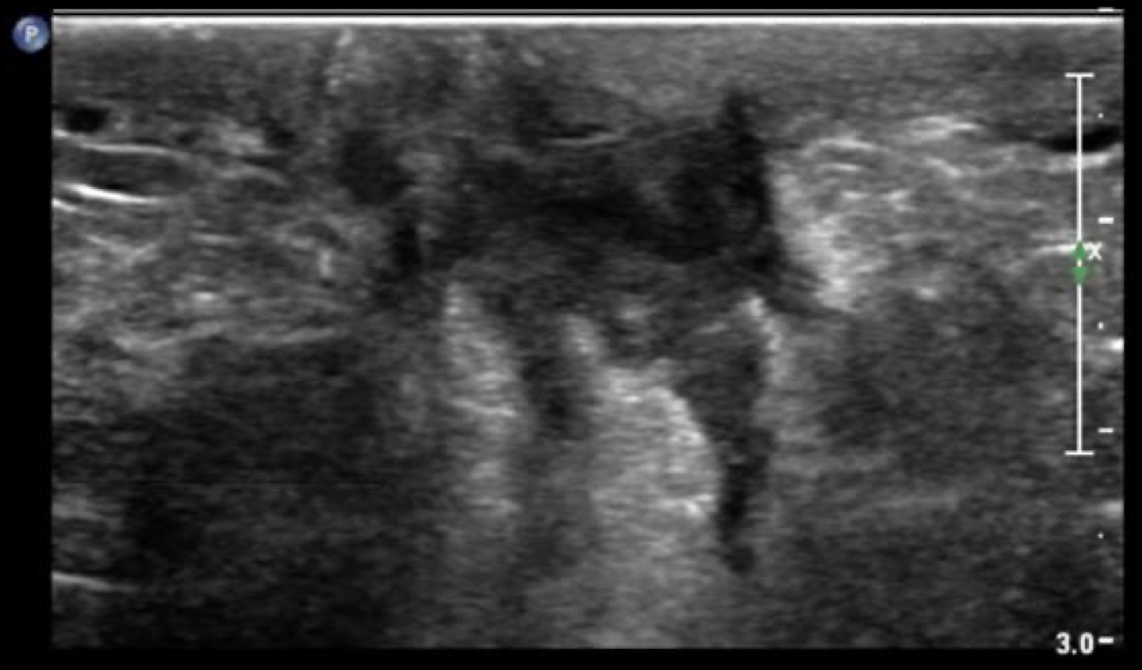

FCC (fibrocystic condition)